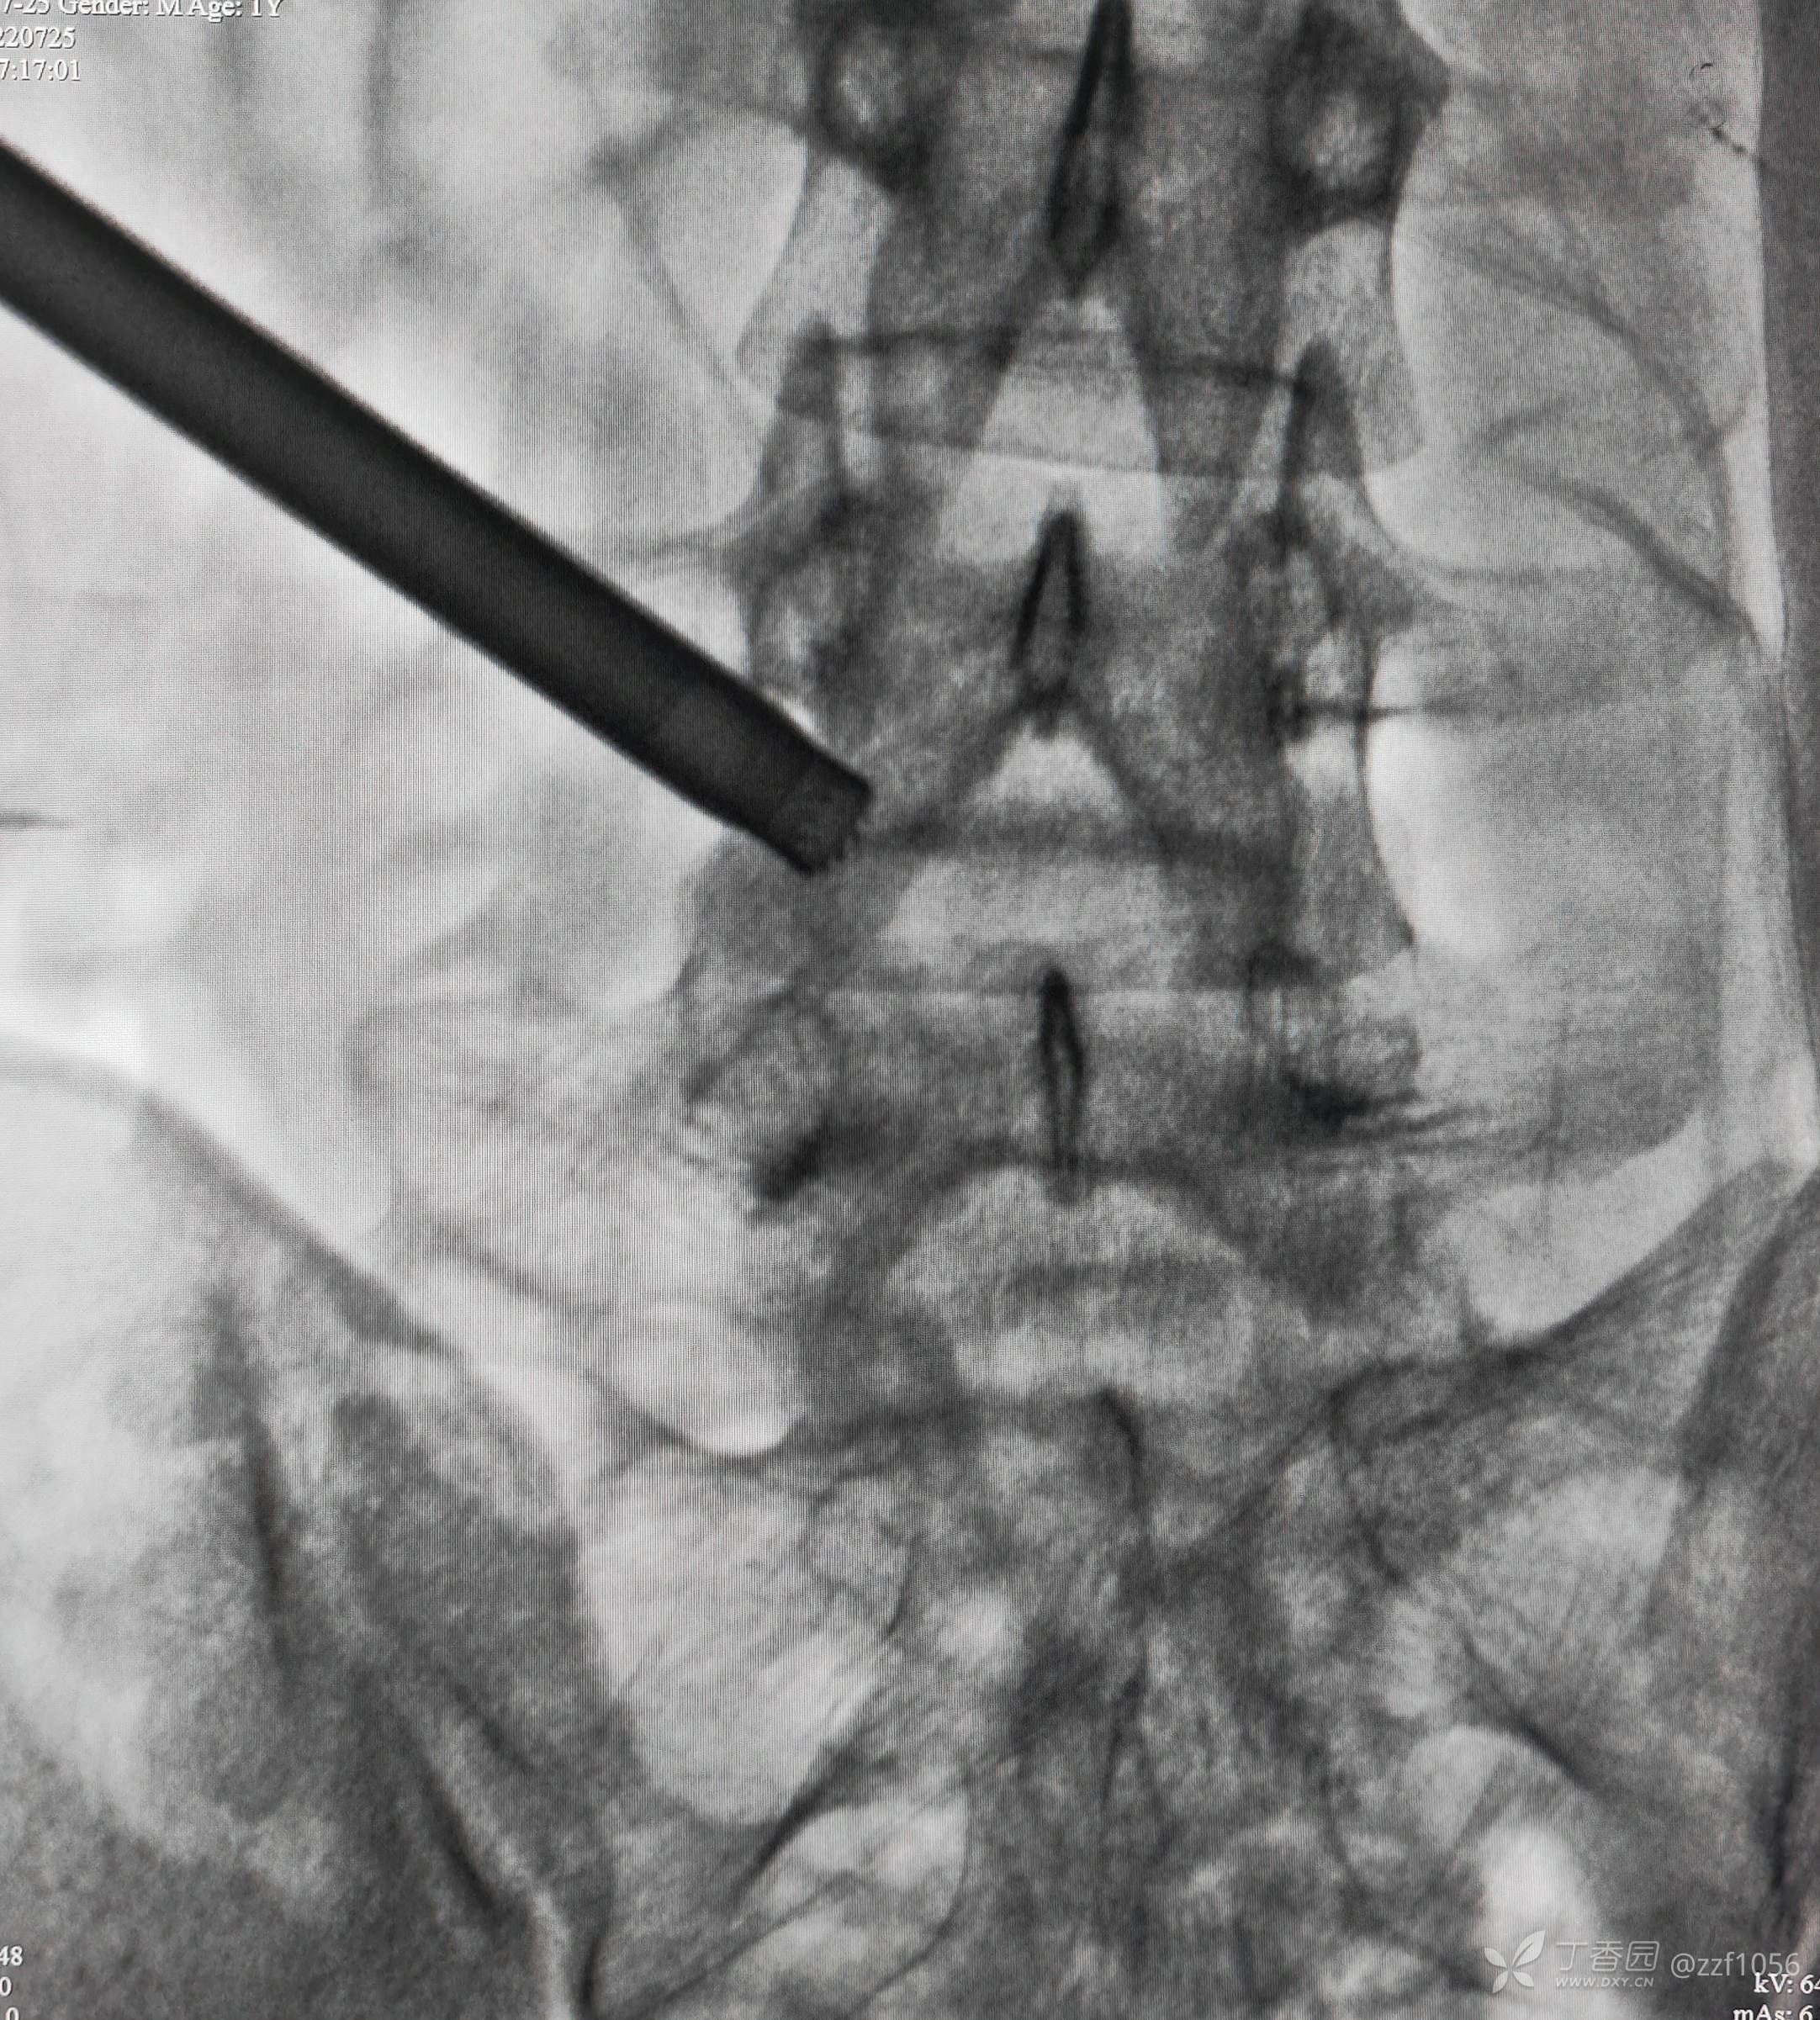

患者男,19岁,高三学生,左下肢疼痛半年,各种保守治疗无效

入院诊断:腰椎间盘突出症(L4/5)